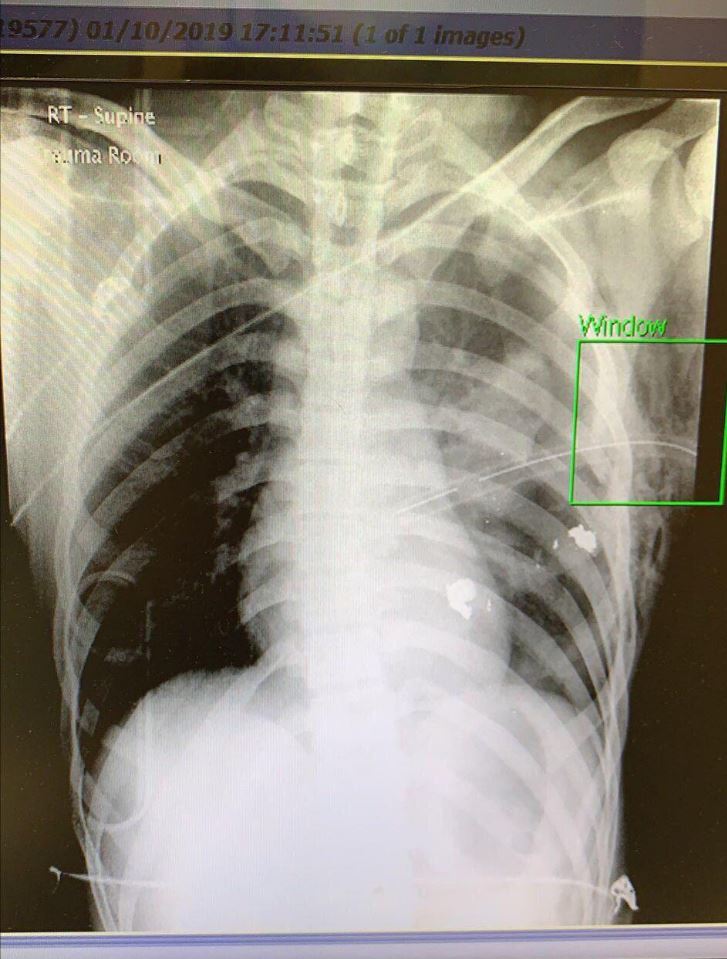

C'est la première blessure par balle depuis le début du mouvement de contestation, au mois de juin. Explication par Le Monde : Hongkong : comment un homme a été blessé par balle Citation : Un homme a été blessé par un tir à balle réelle lors des manifestations qui ont secoué Hongkong le 1er octobre. C’est un policier dont l’unité avait été attaquée par des protestataires qui lui a tiré dessus à bout portant. Le sujet sur reddit.com permet aussi d'avoir quelques infos et retours intéressants. Notamment : - Le manifestant à crier son nom : Un certain Tsang Tsz Kin, agé de 18 ans - Quelques images du protestant, notamment la fuite d'une image rayon X de l'hopital, montrant que la balle s'est arrêté à 3cm du coeur du manifestant - Le maniesftant a été amené à l'hopital "Queen Elizabeth Hospital", dans lequel il reste en situation stable Perso je remarque que, outre le geste absolument impardonnable du policier c'est évident, les manifestants n'hésitent pas à s'en prendre très violemment aux policiers. Meilleur moyen pour que tout parte en couille. Et dans ce contexte de conflit Occident-Chine, y a des tas d'appels (notamment sur reddit), poru que les pays Occidentaux fassent plier la Chine, ou pour aider les manifestants. Perso je me méfie du coup beaucoup du traitement des images et infos sur un sujet très politique L'image rayon X qui a fuité : ![]()